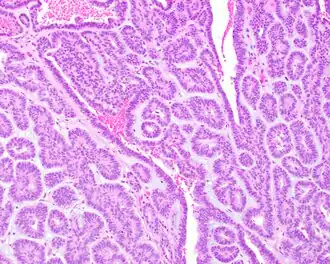

Histologicamente, o adenoma canalicular é caracterizado por ser uma neoplasia benigna composta por epitélio cuboide ou colunar formando canalículos, dispostas em ilhotas ou cordões de células com espaços císticos entre esses cordões.[1] Esse tumor pode infiltrar a cápsula e até mesmo formar tumores microssatélites extracapsulares.[1] O estroma tumoral é composto por tecido conjuntivo frouxo bem vascularizado.[1][2]

Em alguns casos, pode haver focos de células basaloides ou oncocíticas, assim como metaplasia mucinosa.[1][2] No estroma é possível encontrar histiócitos e focos de degeneração ou hemorragia.[1][2]

Necrose é excepcionalmente encontrada, assim como mitoses, estando normalmente ambas ausentes.[1][2] Não há registros de transformação maligna deste tumor, mas ele é ocasionalmente reportado como um tumor híbrido ou de colisão com outra neoplasia.[1][2][5]